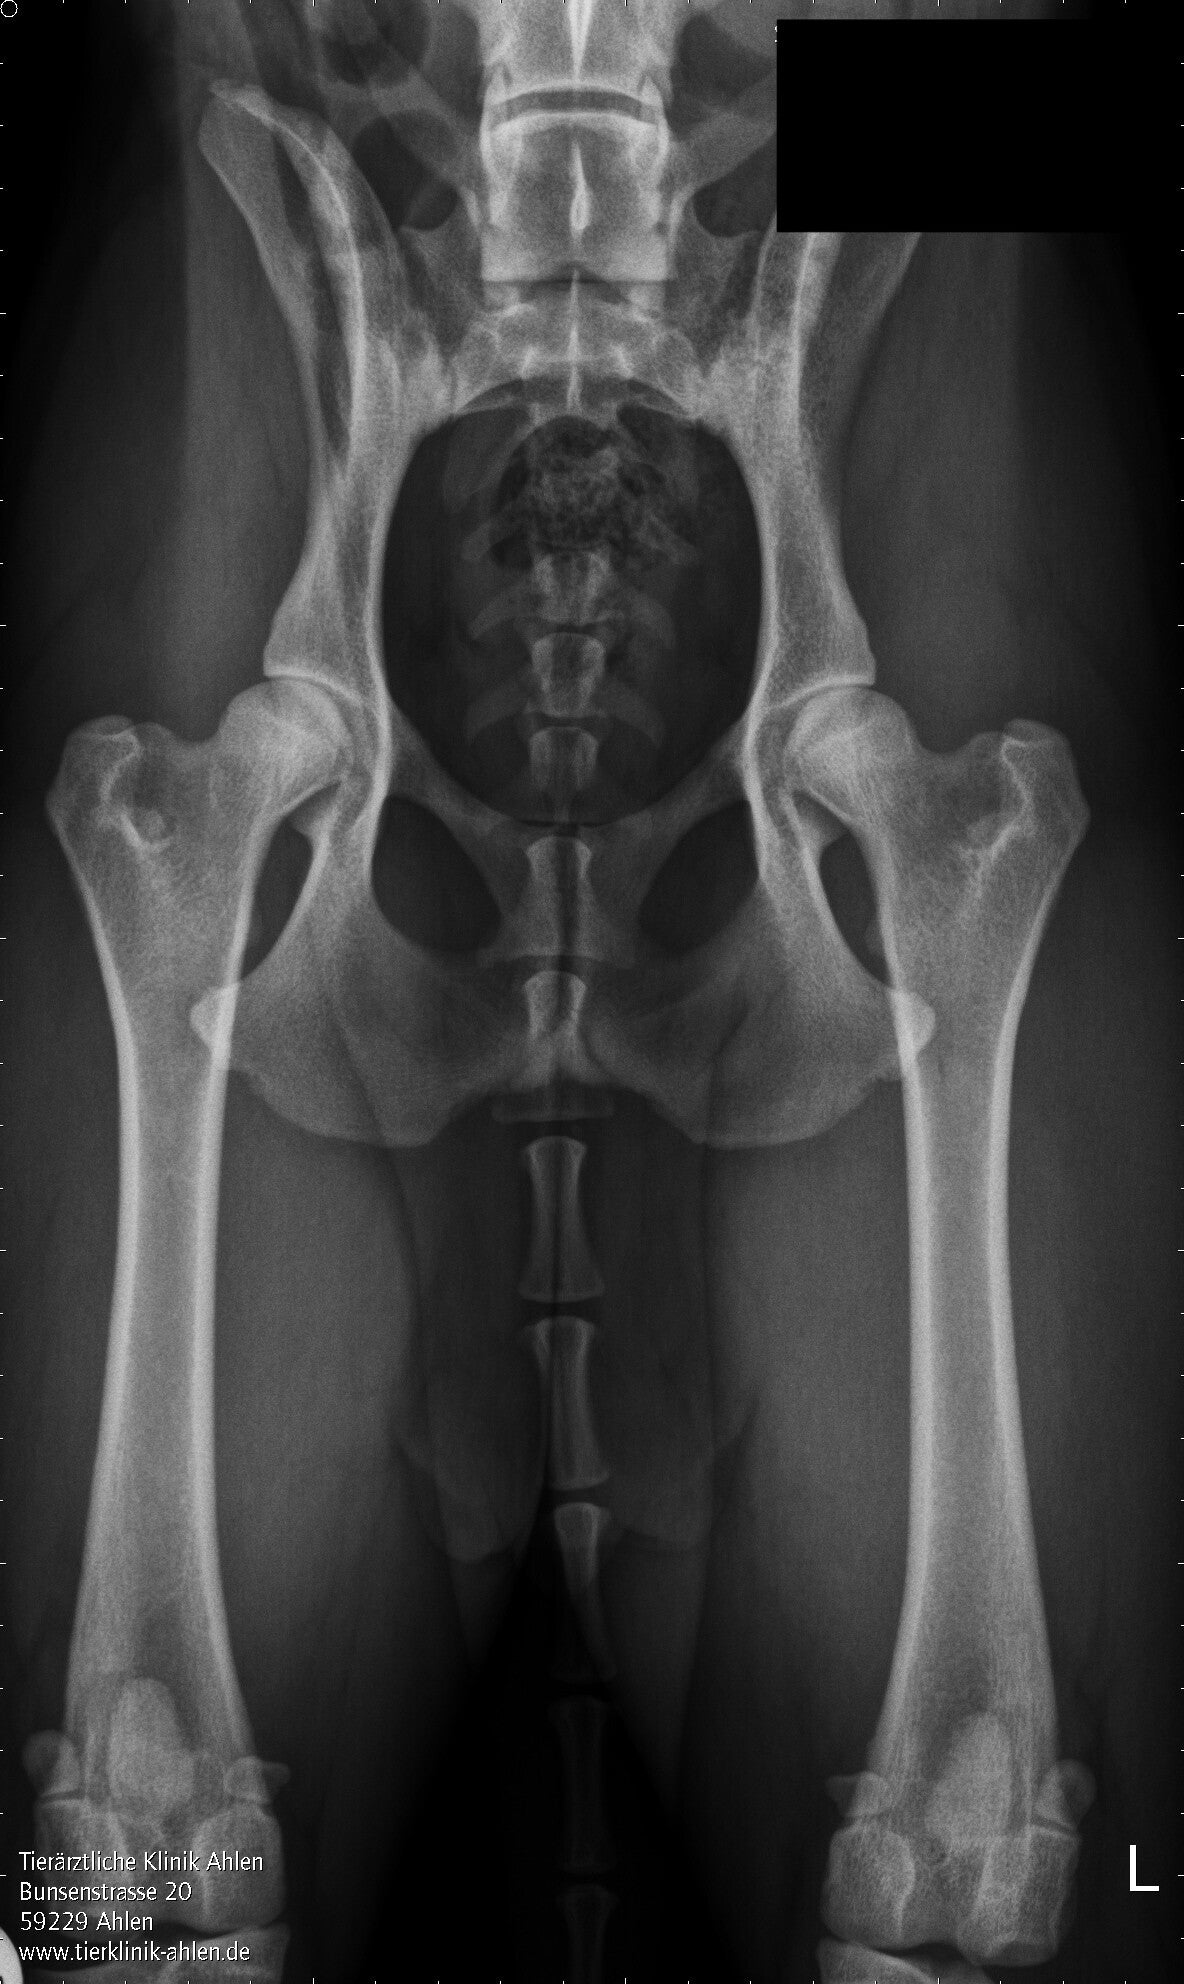

HD-Gutachten

Beurteilung der Hüftgelenke auf Hüftgelenksdysplasie nach FCI-Schema.